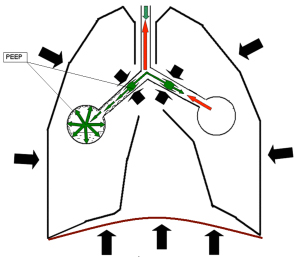

AutoPDKV (AutoPEEP Intrinsic PEEP) akkor jelentkezik, ha beállítása a ventilátor (légzésszám, mennyisége és időtartama inhalációs) nem felelnek meg a beteg képességeit. Ebben az esetben a beteg kezdete előtt egy új inspirációt nem volt ideje, hogy lélegezni a levegő az előző levegőt. Ennek megfelelően, a nyomás a végén a kilégzés (kilégzési nyomás) sokkal pozitívabb, mint az kívánatos volna. Amikor kialakult nyugalom AutoPDKV (Auto PEEP, Intrinsic PEEP vagy iPEEP), alatt elrendezett a koncepció, hogy a nyomás a PEEP értetődő, hogy létrehozza a végén a kilégzés, a ventilátor, és jelzi a teljes PEEP bevezetett Összesen PEEP távon.

Összesen PEEP = AutoPEEP + PEEP AutoPDKV nevezhető angol irodalom:

A modern ventillátor, vagy van egy speciális teszt programot, hogy meghatározza a AutoPEEP.